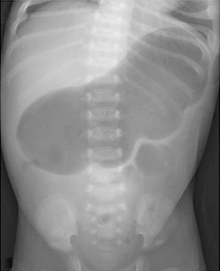

However, in small bowel obstruction, there is too much gas in the small bowel loops compared to the colon. Conversely, in colon obstruction with intact ileocecal valve, there is too much gas in the colon (Figure 3) compared to the small intestine and there is little or no gas in the rectum.5 The lack of gas in the rectum, however, is a late sign of bowel obstruction, so patients who present early in their disease process may have gas in the rectum on radiograph.

Figure 3 Anteroposterior supine abdominal radiograph in a 4-year-old child showing dilatation of bowel with smooth walls with too much gas in colon (haustra can be seen to identify colon) and absence of gas in the rectum suggestive of distal large bowel obstruction at level of rectosigmoid junction probably due to Hirschsprung’s disease.